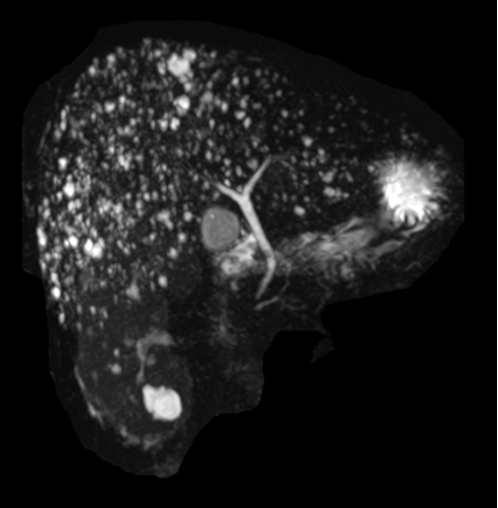

肝脏磁共振见弥漫分布小圆形信号,呈“满天星样”

胆管错构瘤是一种较为罕见的肝脏良性病变。该病变主要发生在肝脏的胆管系统中,由正常组织的异常组合构成,不同于真正的肿瘤,它们不具有侵袭性或转移性。胆管错构瘤通常在影像学检查中偶然发现(如图),由于其临床表现不明显,诊断和处理具有一定的挑战性。